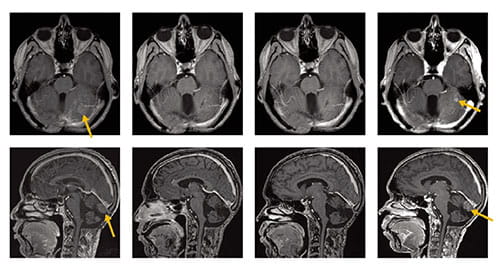

The combined study involved 43 adult and pediatric patients with recurrent medulloblastomas. Investigators conducted brain scans, gene sequencing tests and drug activity evaluations as participants received the drug.

Disease progression ultimately occurred in all patients. However, prolonged disease stabilization occurred in 41 percent of patients in the SHH-MB subgroup. The longest progression-free periods lasted from about six months to more than 15 months.